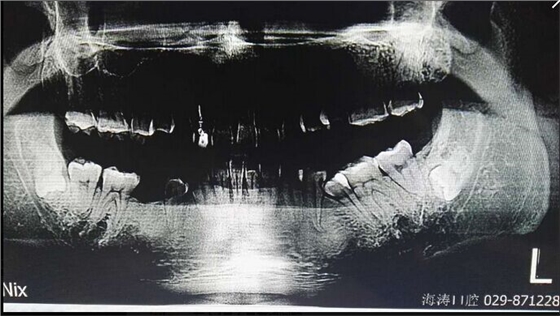

討論四:片子顯示的倒置阻生牙撥牙關(guān)健注意幾點,1.翻瓣后去骨部位盡量離7遠中,別破壞7遠中骨壁,避免損傷7,以去除8根部的阻力為主。2.暴露阻生牙后,用鉆磨斷部分冠根后,用小骨鑿劈裂冠與根,可避免牙鉆因視野而誤傷神經(jīng)。3.冠根裂開后,先用牙挺挺出根部,然后挺出冠部。

提問:對7號牙沒有影響的埋伏智齒,是不是可以不拔?

答:一般情況下,完全骨埋伏阻生牙患者如無不適癥狀不會要求撥牙的,很多時候是口腔內(nèi)其它問題拍片時發(fā)現(xiàn),但醫(yī)生發(fā)現(xiàn)這種情況要告知患者將來可能會發(fā)生什么問題,例如頜骨囊腫,7號牙松動等等,畢竟這個8號牙是潛在的病灶牙,究竟撥與不撥得讓患者作主,我們得盡到告知義務(wù)。往往最后決定撥這類牙的患者都是有各種不適癥狀的。

至于對7號牙暫時沒有影響的埋伏牙,不等于以后永遠不影響。